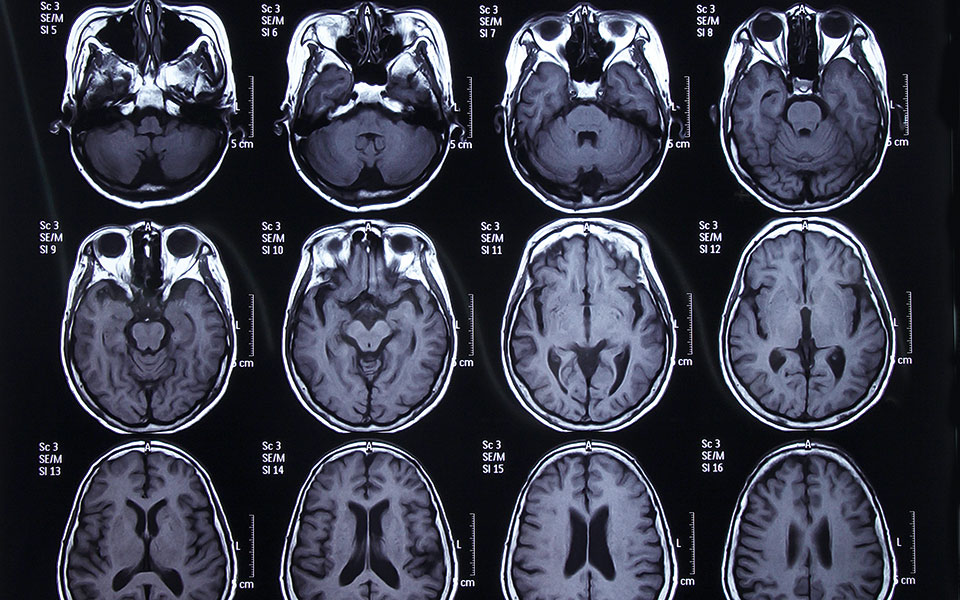

Ποικίλοι στόχοι. Οι δέσμες ακτινοβολίας που κατευθύνονται προς διαφορετικά σημεία του σώματος στην πάροδο των ετών δεν αθροίζονται για να προκαλέσουν σωρευτικό κίνδυνο. «Ανησυχία προκαλείται από την επαναλαμβανόμενη έκθεση των ίδιων κυττάρων, όχι από την έκθεση του καρπού για μια ακτινογραφία, του κεφαλιού για μια αξονική τομογραφία ή της σπονδυλικής στήλης και του ισχίου για μια μέτρηση οστικής πυκνότητας», επισημαίνει ο δρ Hammer.

– 2,1 mSv σε μια αξονική τομογραφία κεφαλής,